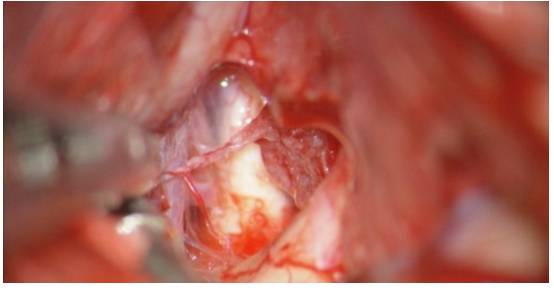

图7. 左侧扩大翼点开颅,切除床突后暴露肿瘤组织。在该病例中,大肿瘤由侧裂向外侧延伸。通过腰大池缓慢释放约40ml脑脊液后(每次释放10ml),可将肿瘤从蝶骨翼硬脑膜外侧游离出来,并电凝其内侧的硬脑膜附着点。该操作是手术中非常关键的一步,通过彻底阻断肿瘤血供,从而避免频繁的止血操作,加快后续的肿瘤切除过程。

图8. 笔者会沿着前颅窝继续阻断肿瘤血供,同时需注意视神经的大致位置,以避免热损伤的发生。脑脊液引流,侧裂分离和吸引器的合理使用,可避免使用固定脑牵开器。

图9. 对实性肿瘤,用超声吸引器(左图)进行去核和分块减压,而对较软的肿瘤组织,用双极电凝、吸引器和垂体咬钳进行减压。接着,笔者会轻轻地牵拉肿瘤包膜,使得其塌陷入已切除的肿瘤核心处(右图)。保持在肿瘤包膜内操作是非常重要的,否则会使得粘附在肿瘤内侧脆弱的脑血管结构受损风险增加。超声吸引器使用时需远离关键血管结构,否则即便没有直接接触,仍可能导致无法修复的血管损伤。

图10. 此时,在部分肿瘤减压,获得更多的操作空间后,笔者会进一步打开侧裂远端,辨别粘连在肿瘤上极和后极的M2分支血管。笔者还会沿着蝶骨翼,轻柔地向后方牵动肿瘤,以便发现或估计ICA在颅底的位置。这两步可以帮助笔者估计MCA分支,包括M1段,沿着肿瘤内侧包膜的走形,而此处正是笔者的盲点。